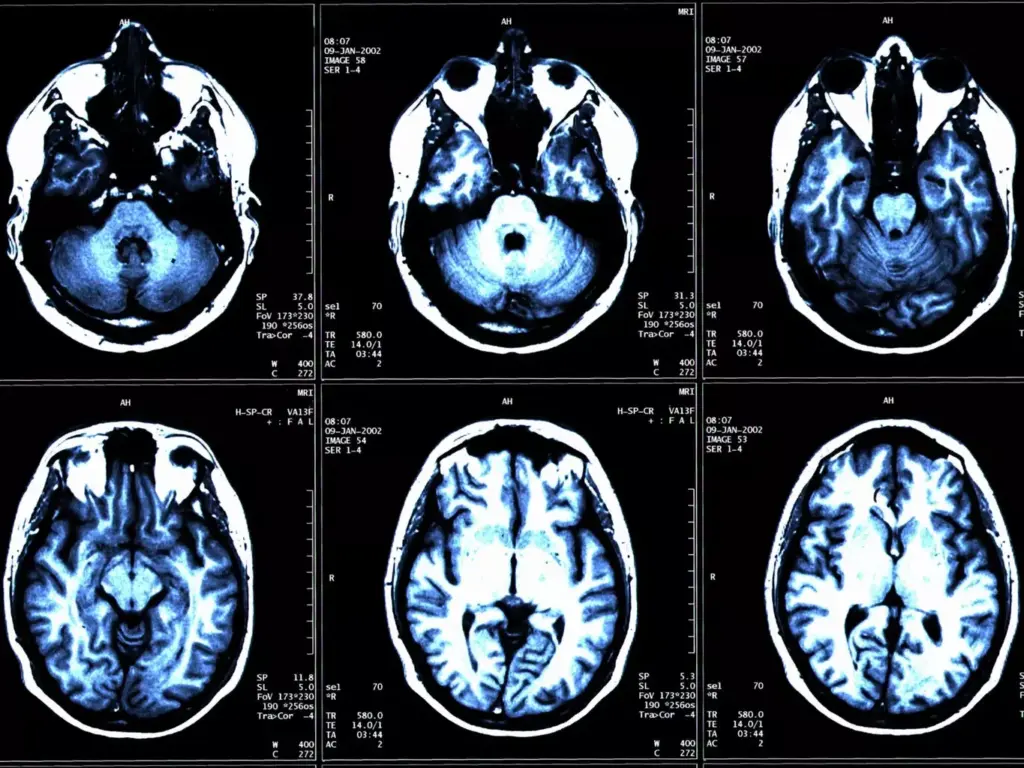

Advanced imaging is key in diagnosing and staging brain tumors. We use different imaging methods to see the tumor and its area.

Magnetic Resonance Imaging (MRI) is a top choice for brain tumors. It gives detailed brain images. This helps us see the tumor’s size, location, and details.

Computed Tomography (CT) scans are used too, mainly in emergencies or when MRI is not available. CT scans show the tumor’s structure and its effect on brain tissue.

Advanced imaging techniques like MRI and CT scans are vital in brain tumor staging. They help determine the tumor’s characteristics, location, and extent. This information guides treatment decisions.